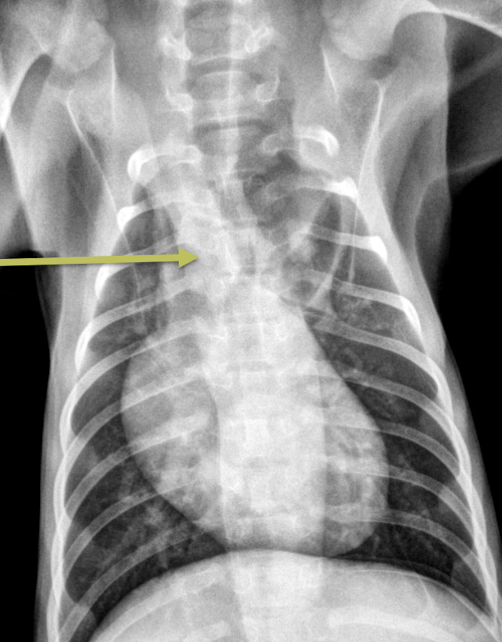

A

Persistent right aortic arch

What is a key finding for persistent right aortic arch?

Focal leftward deviation of the trachea